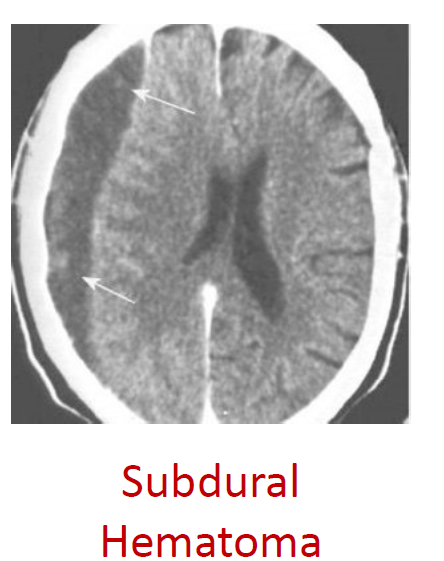

• A subdural hematoma is from sudden acceleration-deceleration (someone falling and hitting their head). Veins traveling from the subarachnoid space to the superior sagittal sinus can be torn from the shear forces. Blood will pool in the subdural space between the dura and arachnoid. Bleeding may be slower because veins have lower pressure. Subdural hematomas have a crescent-shape on MRI (because the dura is still attached to the skull)

• Label the type of hematoma

A) subdural hematoma